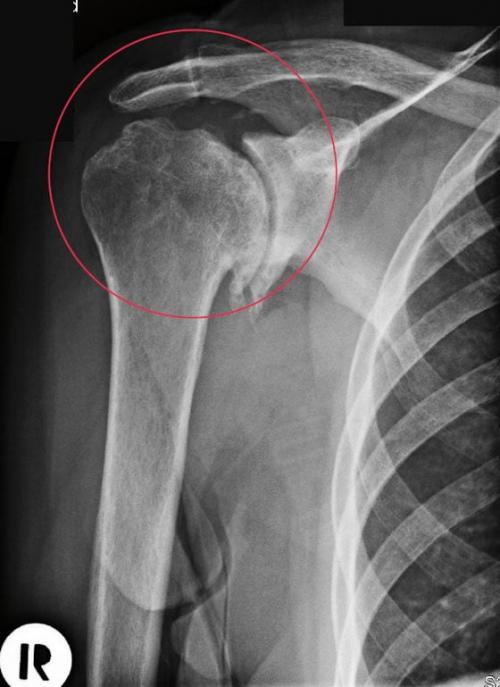

Диагноз на рентгене.

Головка плечевого сустава, пораженная артрозом.

В сочленяющихся суставных элементах подвижного соединения плечевой кости с лопаткой появляются грубые костные наросты, которые со временем ограничивают степень свободы движений всего плечевого механизма.